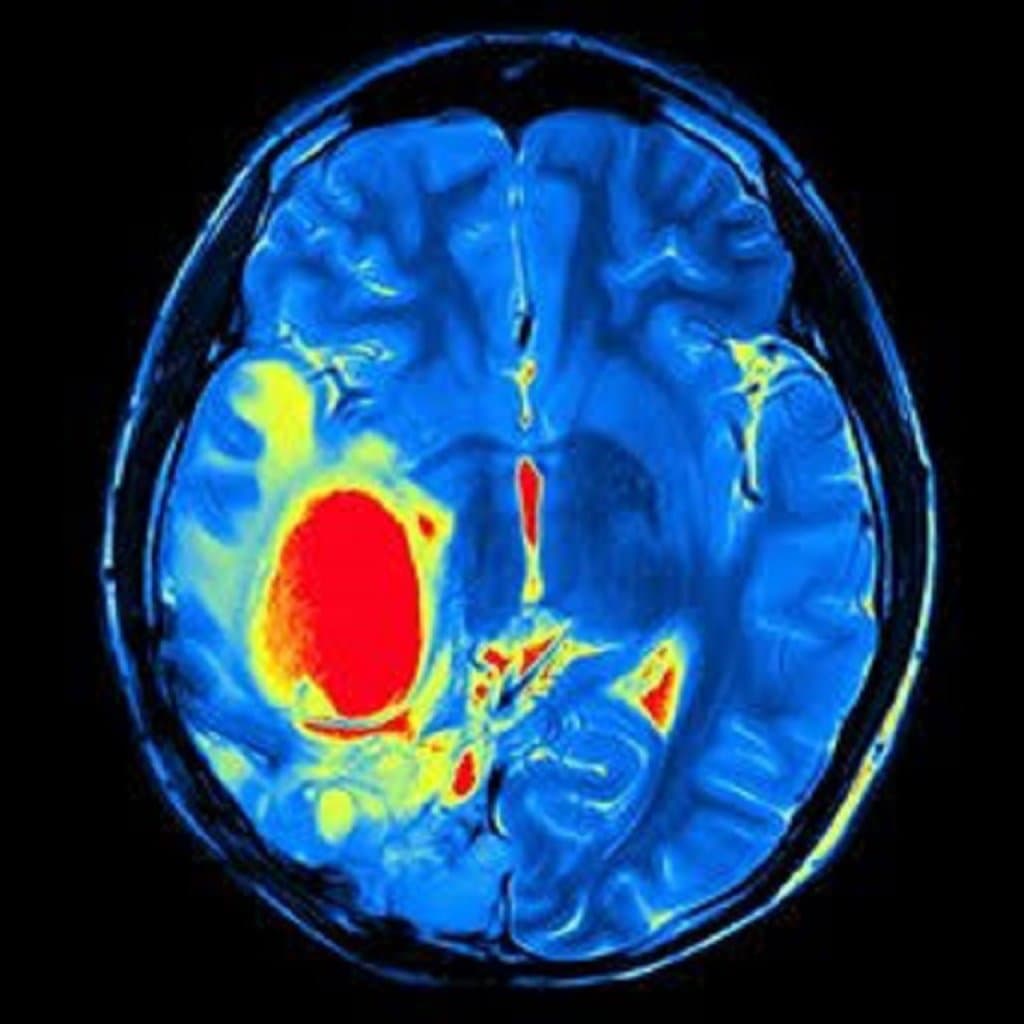

Cərrahlar əməliyyat zamanı yüksək dəqiqlik təmin etmək üçün tez-tez əməliyyatdaxili görüntüləmə üsullarından istifadə edirlər. Bu texnologiya, şişin yerini və ətraf toxumalarla əlaqəsini real vaxt rejimində təsvir etməyə imkan verir. Beləliklə, cərrah şişi daha yüksək dəqiqliklə və sağlam toxumalara minimum zərər verərək çıxara bilir.